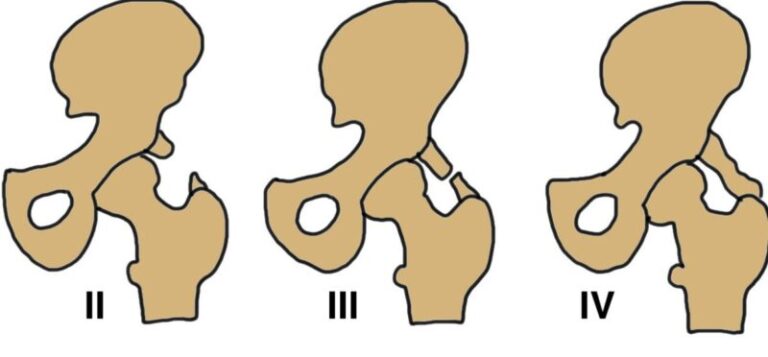

Biểu hiện viêm khớp cùng chậu giúp chẩn đoán sớm, hình ảnh viêm khớp cùng chậu có thể chia thành 4 giai đoạn:

- Giai đoạn 1: khe khớp hẹp, diện khớp hơi mờ.

- Giai đoạn 2: khe hẹp, bờ nham nhở.

- Giai đoạn 3: diện khớp mờ, nham nhở, dính khe khớp ở phần trên.

- Giai đoạn 4: khe khớp dính hoàn toàn không còn ranh giới.

Viêm khớp cùng chậu ở giai đoạn 3 và 4 ở cả 2 bên mới có giá trị chẩn đoán.

- Viêm khớp cùng chậu 2 bên (độ 2-4) hoặc độ 3 – 4 một bên.